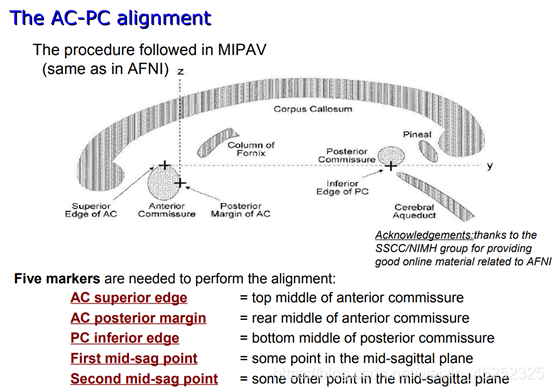

前连合-后联合目的:(AC-PC)

AC-PC:为前联合(anterior commissure, AC)后缘中点至后联合(posterior commissure, PC)前缘中点的连线,又称AC-PC线。脑立体定向手术和X-刀、Y-刀治疗多以此线为准,故脑立体定位断层解剖研究多以此线为基线。

首先我们要知道立体定向脑图谱与其他解剖学脑图谱的不同点。我们都知道,在地理学上,两座山峰高低的比较是以海平面为基础的。那么人脑的比较的基础又是什么呢?立体定向脑图谱是以前连合与后连合的连线(AC-PC)为基准的,因为研究已经表明不同人脑的AC-PC没有显著性差异。以AC-PC中点为原点我们可以建立三维坐标系,在这个三维空间中获得的不同人脑的数据就可以进行比较了。因此,立体定向脑图谱——以AC-PC线为基准线获得的脑图谱被称作是标准的脑图谱。

目标:确定5个点的位置

对于这5个点的介绍(图中显示的是矢状面):

(2) 第一个目标标记AC上中部和后中部

AC:

•矢状位:在穹窿下方胼胝体底部寻找AC

•冠状:寻找“胡须”

•轴向:寻找半球间的连接

① 使AC在十字准线的焦点处居中(轴向和冠状)

② 向上移动,直到AC在轴向视图中消失,然后向下移动1像素

③ 设置AC上边缘(superior edge)

④ 将焦点移回AC中间

⑤ 向后移动直到AC在冠状面上消失;然后往前1像素

⑥ 设置AC后缘(posterior margin)

(4)第二个目标是标记PC inferior edge

•这更难,因为PC在1毫米分辨率下显示不好

•幸运的是,PC始终位于脑导水管的顶部,这确实显示得很好(至少,如果脑脊液被MRI脉冲序列适当抑制的话)

因此,如果你看不到PC,就在脑导水管顶部找到中矢状位,标记为PC下缘(inferior edge)

(5) 第三个目标是标记两个中矢状点(胼胝体上方)(这一步在文中没有详细描述,所以有点模糊,参考另一篇参考)

First midsagittal point和Another midsagittal point,要求二者之间距离在20mm以上,一般就选择在和AC,PC同一矢状面上(在实践中,SG1和SG2的好候选者通常远离AC和PC,彼此之间也远离)